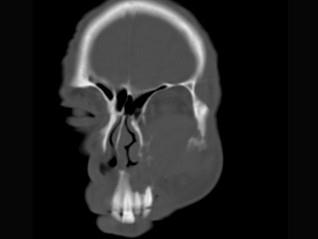

问题 男,65岁,左眼球突出近一年,鼻涕带血,面颊部隆起,同时面颊部有麻木感,CT检查如图,最可能诊断为 ( )

选项 A、上颌窦癌 B、骨肉瘤 C、上颌窦血管瘤 D、上颌窦囊肿 E、上颌窦息肉

答案 A